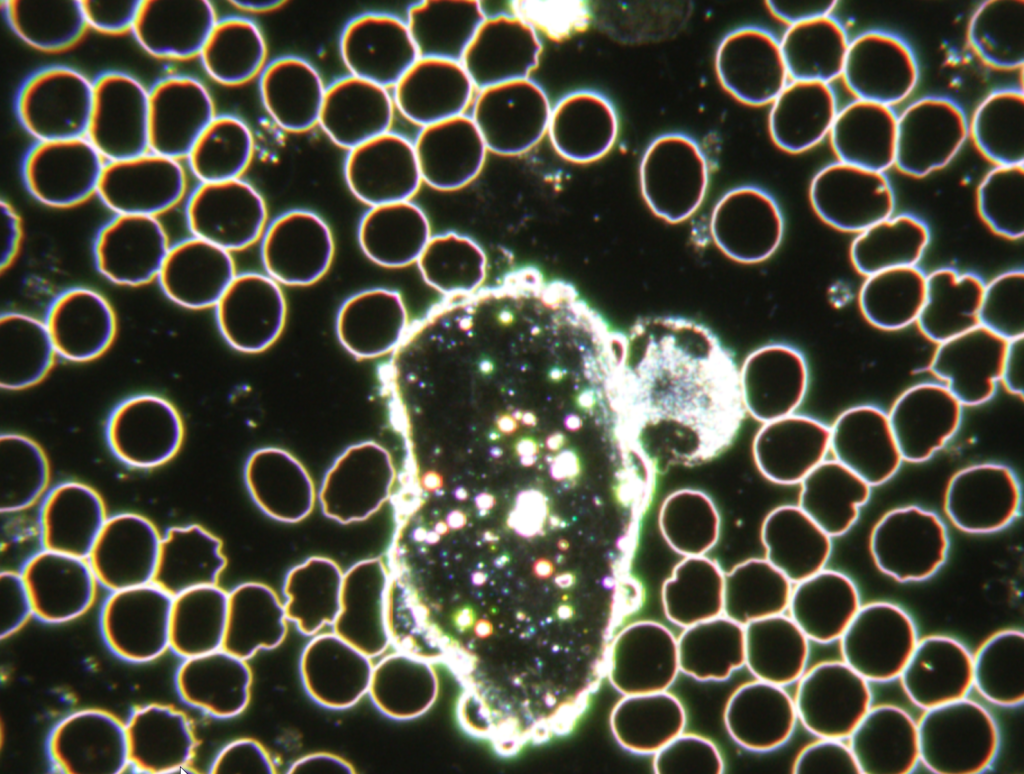

Manch Einer fragt sich warum werde ich krank und der Andere nicht. Mikroorganismen können sich unter bestimmten Verhältnissen einfach besser entwickeln. Ein gestörtes Körpermilieu ist der beste Nährboden für Erkrankungen. Genau hier setzt diese Untersuchungs- und Behandlungsmethode nach Prof. Dr. Enderlein an. Bei diesem Diagnoseverfahren wird mit Hilfe des Dunkelfeld-Mikroskops ein Tropfen Blut untersucht. Aufgrund der speziellen physikalischen Vorraussetzungen des Dunkelfeld-Mikroskops können Phänomene im Blut erkannt werden und so Rückschlüsse auf Veränderungen im Körpermilieu gezogen werden. Es wird die Anzahl, Form und Beweglichkeit der Weißen und roten Blutkörperchen untersucht, die Lage der Blutblättchen beurteilt und Erscheinungsformen im Plasma bestimmt.

Beispiele: